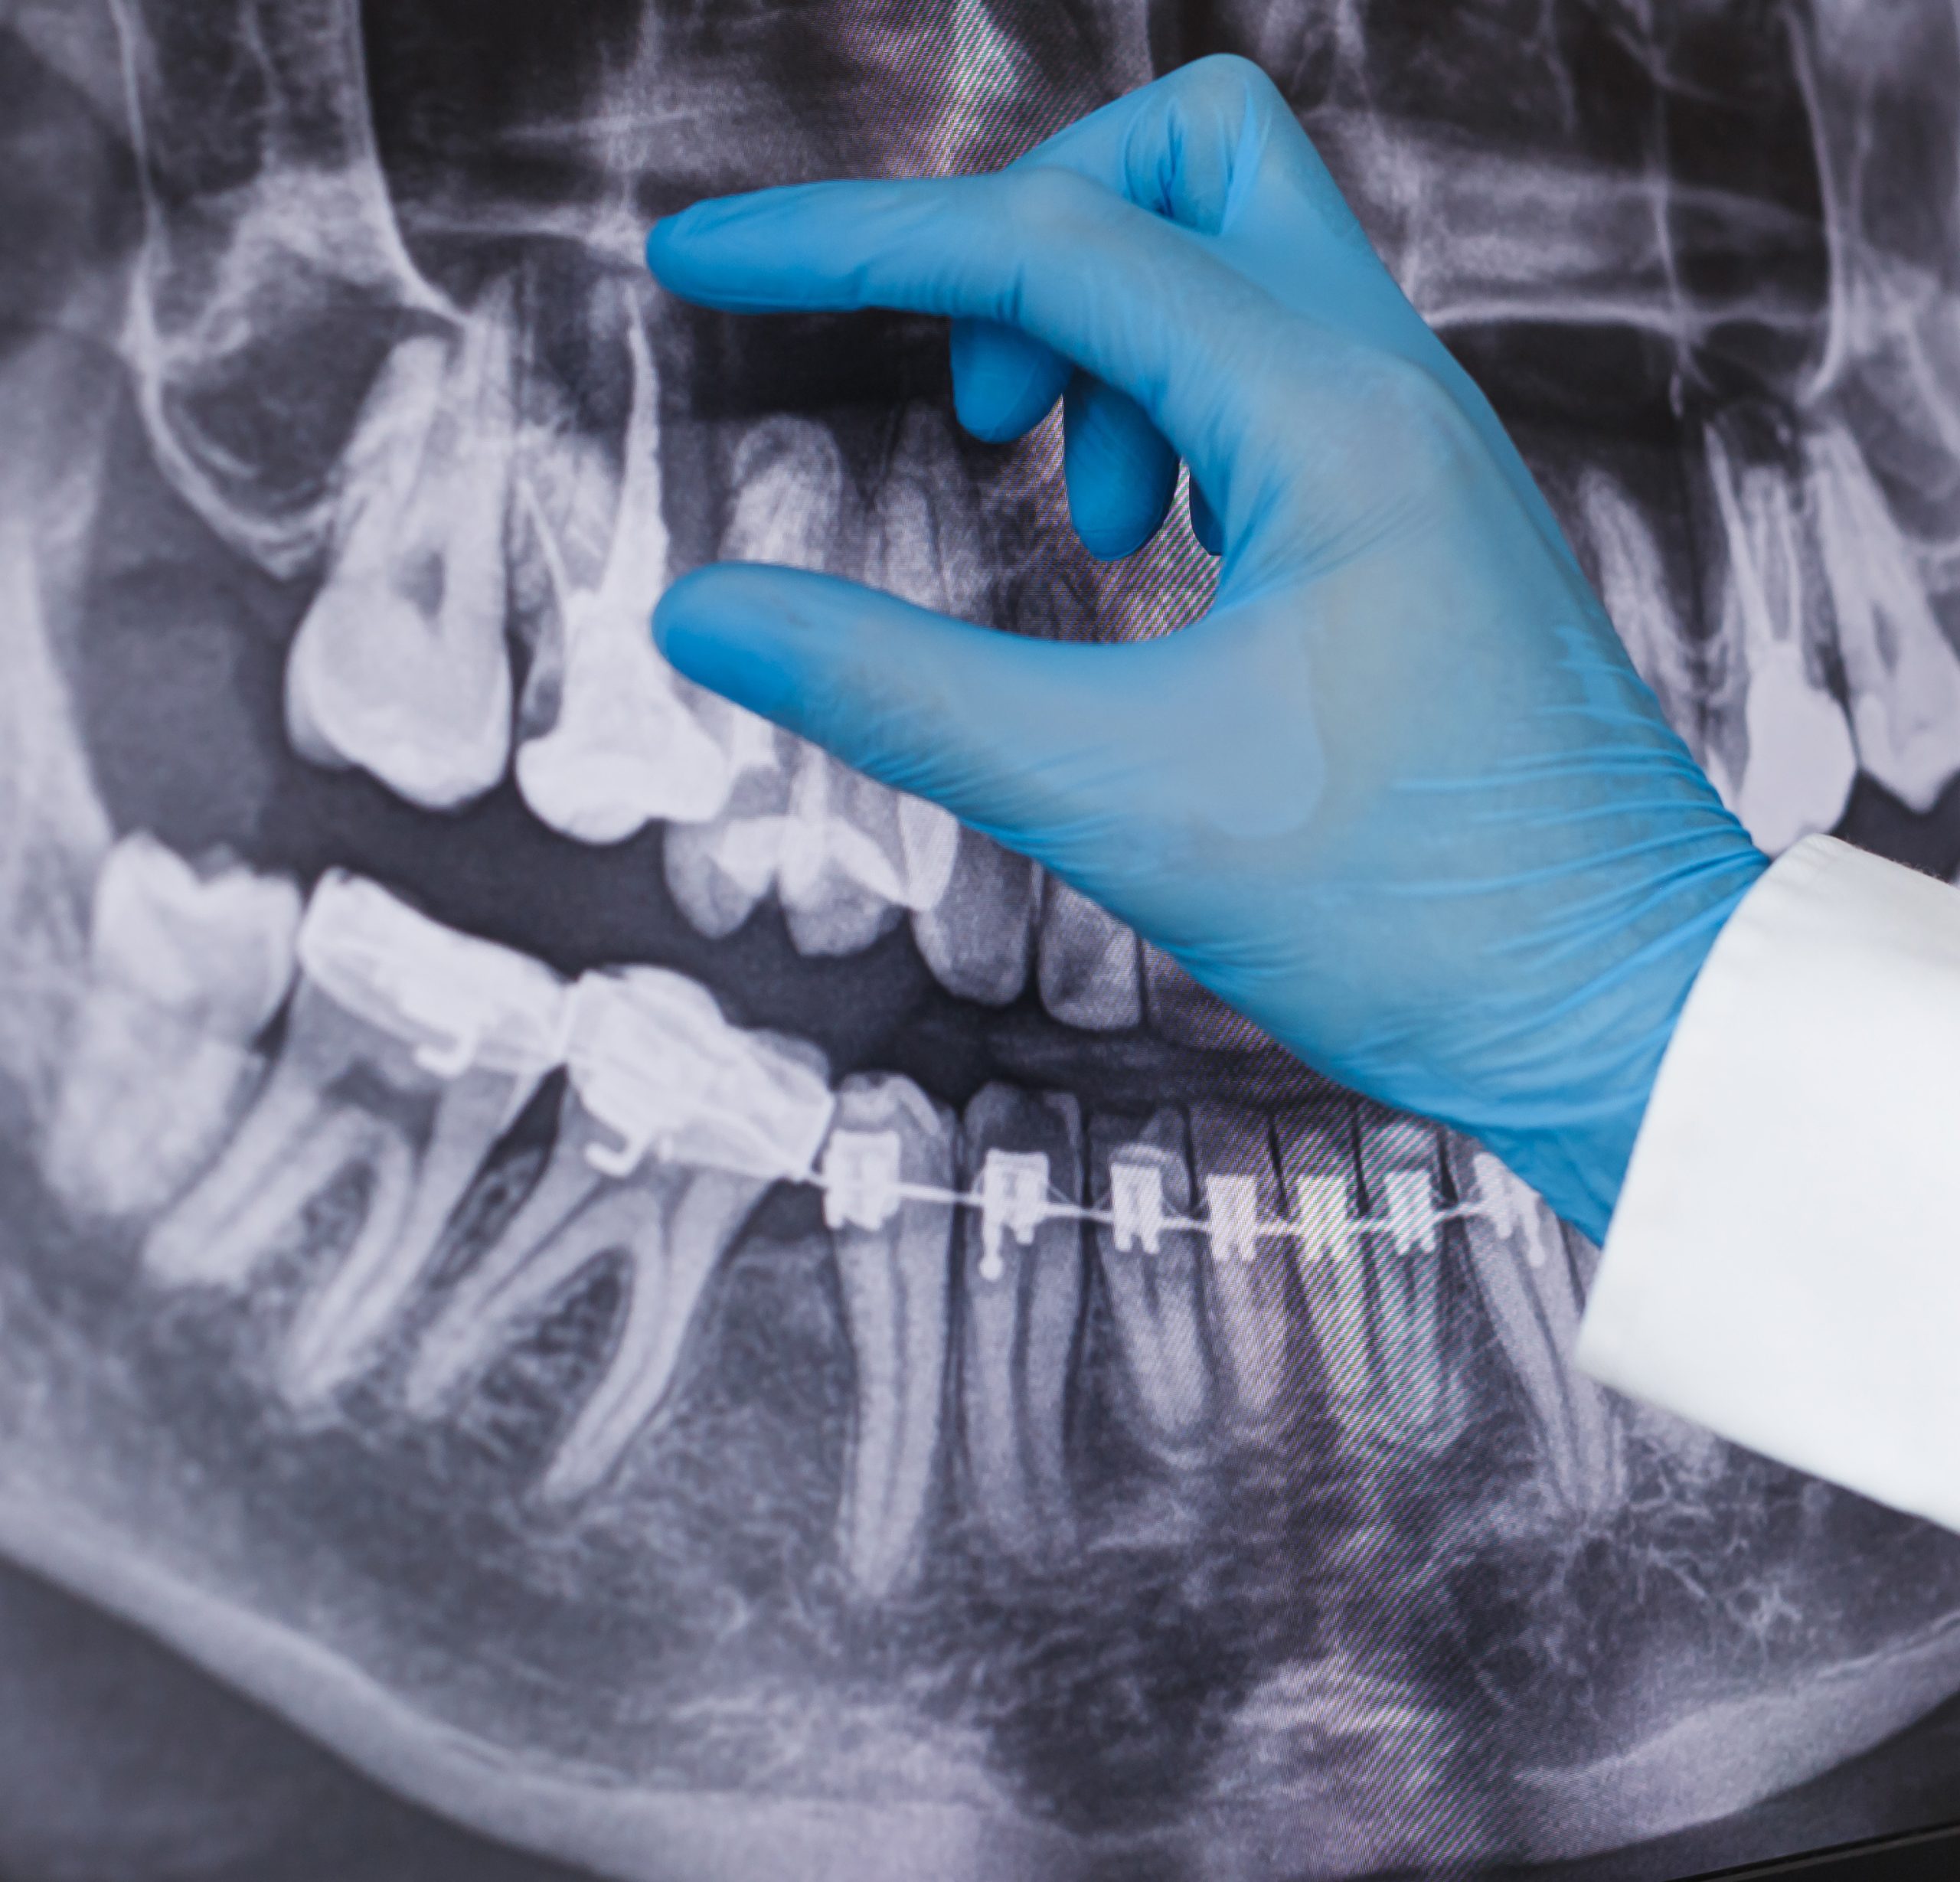

1. Radiografia panoramică

• Oferă o vedere completă a maxilarului superior și inferior

• Permite evaluarea dinților, articulațiilor temporomandibulare și structurilor osoase

• Utilă pentru: planificarea implanturilor, evaluarea dinților incluși și screening general

Clinica Zahn Art este dotată cu Planmeca ProMax

Acesta este  un sistem CBCT produs de Planmeca, lider mondial în imagistică dentară.

Tehnologia Planmeca Ultra Low Dose™ (ULD) permite realizarea investigațiilor 3D cu o doză de radiație semnificativ redusă, menținând în același timp o calitate a imaginii optimă pentru diagnostic. În anumite indicații, doza poate fi chiar mai mică decât cea a unei radiografii panoramice 2D.

Protocolul ULD respectă principiile internaționale ALADA/ALARA (expunere cât mai redusă, dar suficientă pentru un diagnostic corect) și permite ajustarea parametrilor în funcție de fiecare pacient și de fiecare caz clinic.

CBCT-ul este esențial în planificarea implanturilor, tratamente endodontice complexe, chirurgie dento-alveolară și ortodonție, oferind o imagine tridimensională precisă a structurilor anatomice.